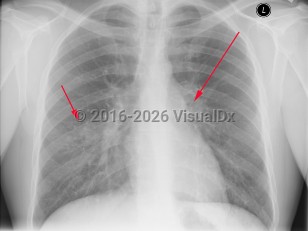

The tubercular bacilli from the infective droplet are taken up by the alveolar macrophages, particularly in the upper and mid-lung zones, which have the highest air flow rates. The breach of the bacteria into the subpleural interstitium causes a local inflammation and consolidation with an exudate and cellular infiltrate. This hallmark of primary pulmonary infection is called the Ghon focus. The bacilli are then rapidly taken up by the mediastinal lymph nodes (hilar and/or paratracheal), resulting in their enlargement and liquefaction, which liberates bacilli that can spread hematogenously throughout the body, seeding different organs. The Ghon focus and the mediastinal lymph node enlargement form the primary or Ranke complex. In most patients, the infection remains latent, being forever contained by the development of cell-mediated immunity that results within 3 weeks to 3 months in a positive skin (tuberculin) test. However, in 5%-10% of patients, mostly within 2-3 years, this initial infection evolves toward active TB. This progression is more common in immunosuppressed states such as AIDS and in children younger than 5 years. While pulmonary TB is the most common form of TB in adults and children, extrapulmonary TB can occur in any age group, although it is more common in younger age groups (eg, tuberculous lymphadenitis).